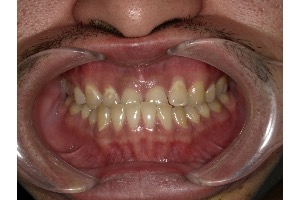

医院ブログ 2025/07/19【歯列矯正】被せ物がたくさん入っていても矯正治療はできる?